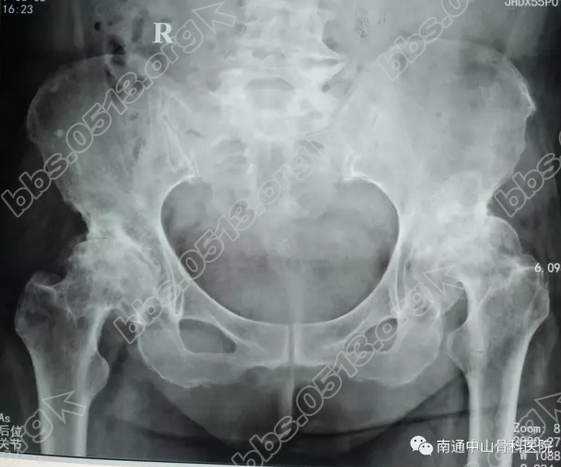

王女士今年已有67岁了,2年前她的双髋部出现了疼痛,休息一阵后病情又能得到缓解,王女士对此便不以为意。之后拖延的期间内,反反复复的疼痛一次次的加重,左侧较右侧疼痛更为明显,负痛的王女士逐渐出现了跛行。去了医院一检查,诊断为:双侧股骨头无菌性坏死

1.png

2017年6月5日,王女士在家人的陪同下来到了我院。来到我院后,我院医生对她进行全面详细的检查,确诊为:两侧股骨头缺血性坏死(左侧为重),双侧髋关节骨性关节炎,颈椎病,腰椎间盘突出症9 s4 x, I& a7 q) _